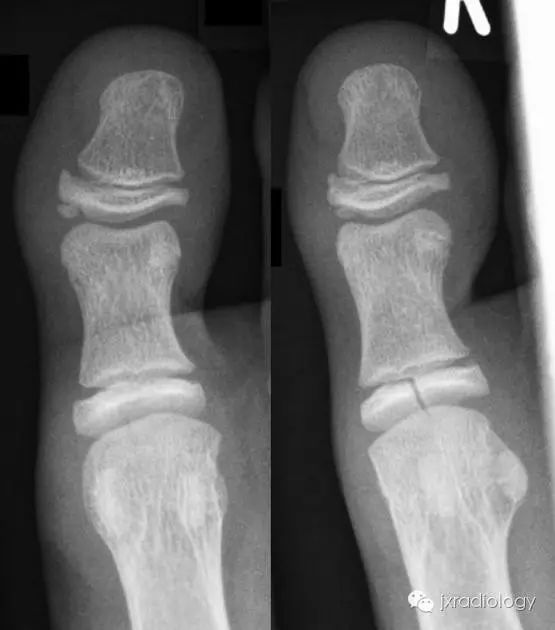

骨骺裂是一种正常变异。它可以是单侧或双侧,最常见的部位是足的第1趾近节趾骨的骨骺。

X线平片显示骨骺见透亮状裂隙影;透亮影的边缘是可变的,可能是锐利的或不规则的。骨骺裂可保留至生长板的融合。

病例图片:骨骺裂